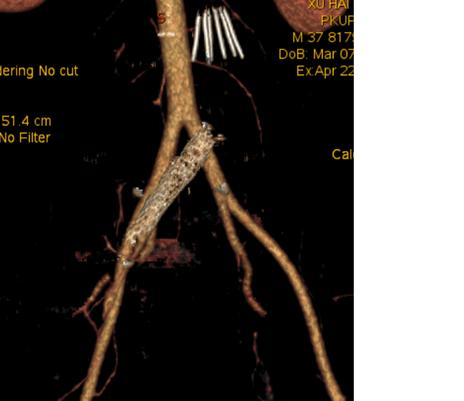

三个病例经过腹盆腔增强CT发现左侧髂总静脉受压闭塞。

箭头所示为几乎消失的左侧髂总静脉

其中第一例还合并左侧髂内动静脉瘘。

与髂内动脉同期显影的髂内静脉